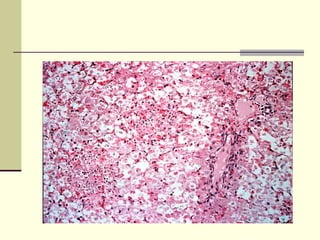

Focal necrosis and multifocal

degeneration

PM lesions.

Focal or generalised hepatic necrosis (white

The yellow appearance and petechial hemorrhages

are characteristic of hepatic necrosis